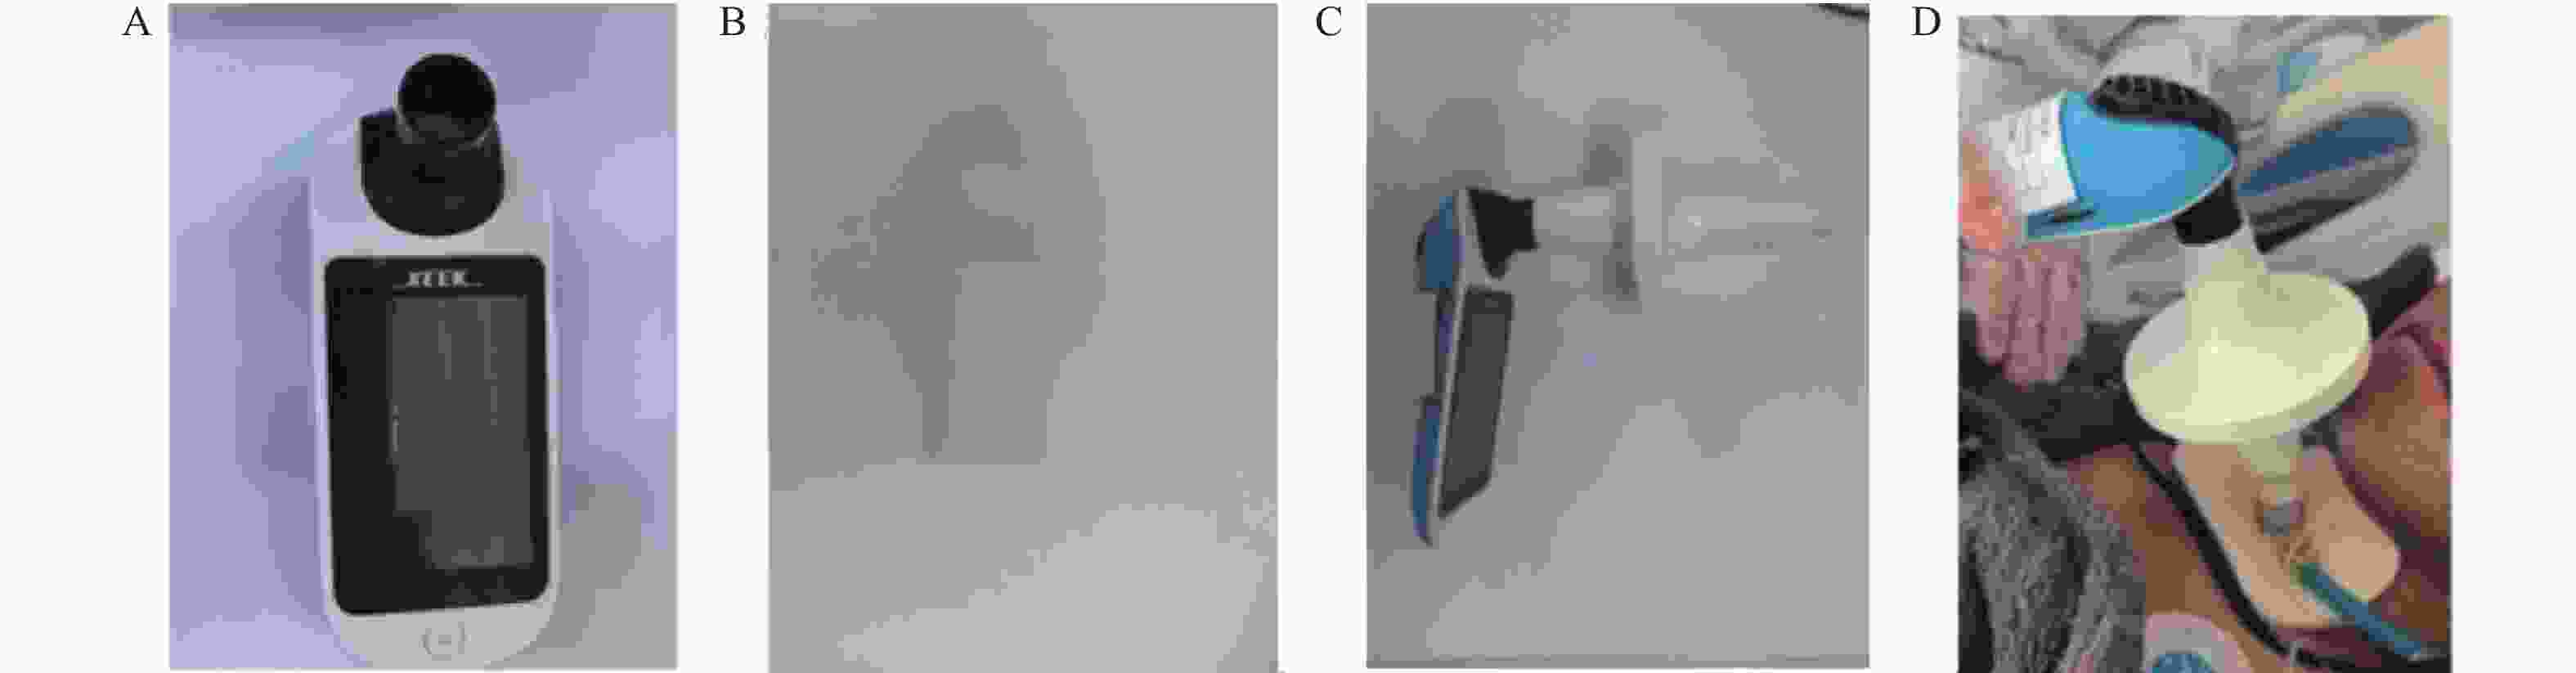

图  2  反射性咳嗽峰流速的测量图

A:赛克便携式肺功能仪(型号:X1);B:3D打印的转接头;C:连接方式;D:RCPF的测量方式。

Figure  2.  Measurement of reflex cough peak flow